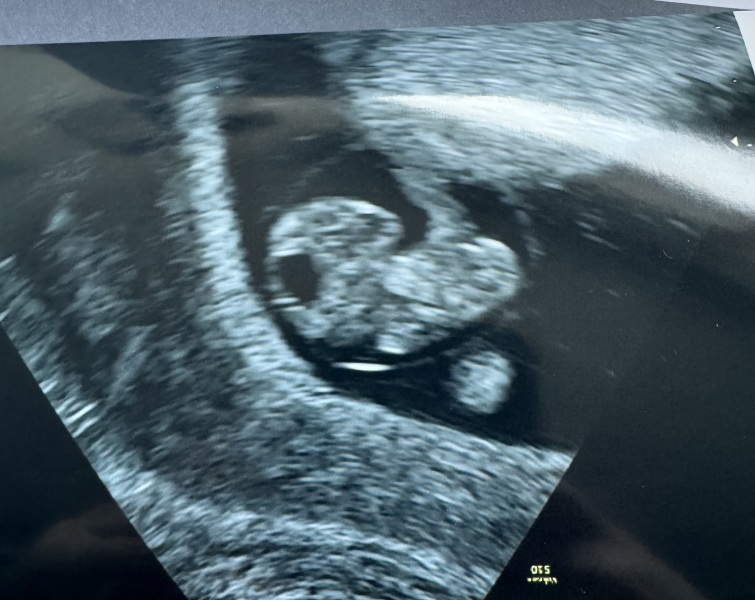

FuppinNora · 12/02/2024 21:08

Had my scan this evening and just wow 😍

10 + 5 is the date she gave me as I wasn't 100% sure when my last period was!

Arms and legs jiggling about. Just makes it real. DH got teary, I think it hit home tonight.